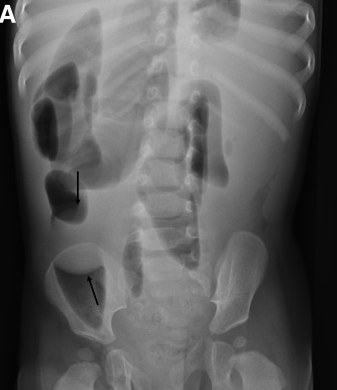

Z Patel et al. Gastroenterol 2021: 161. https://doi.org/10.1053/j.gastro.2020.10.051. Full text: An Unusual Case of Small Bowel Obstruction

Case report of a 10 month old who developed a small bowel obstruction due to an “Orbeez” ball. “Orbeez balls are small polymer beads that absorbs water and expands, it can get up to 150 times their original size. When left out of water, the beads shrink back down to its original size. They were originally invented as a way to keep moisture in soil for plants. They are hugely popular with children and often used as toys, flower holders, air fresheners, light jars, and objets d’art in the house.”